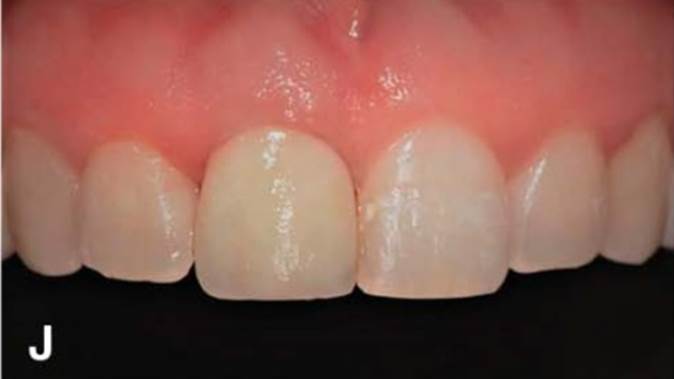

Clinical case: Replacement of fractured central incisor (#11) with immediate implant

& Root Membrane Technique

- Courtesy of Dr. Miltiadis Mitsias, Greece -

Keywords

AnyRidge, Root Membrane Technique, retrospective study, long-term study, immediate implants, bone resorption, bone preservation, Dr. Miltiadis Mitsias,survival, success, maxillary anterior, single replacement

Products:

AnyRidge implant system, Root Membrane kit